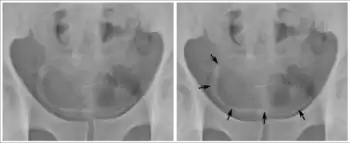

Cancer of the bladder is known as bladder cancer. It is usually due to cancer of the urothelium, the cells that line the surface of the bladder. Bladder cancer is more common after the age of 40, and more common in men than women;[33] other risk factors include smoking and exposure to dyes such as aromatic amines and aldehydes.[33] When cancer is present, the most common symptom in an affected person is blood in the urine; a physical medical examination may be otherwise normal, except in late disease.[33] Bladder cancer is most often due to cancer of the cells lining the ureter, called transitional cell carcinoma, although it can more rarely occur as a squamous cell carcinoma if the type of cells lining the urethra have changed due to chronic inflammation, such as due to stones or schistosomiasis.[33]

Investigations performed usually include collecting a sample of urine for an inspection for malignant cells under a microscope, called cytology, as well as medical imaging by a CT urogram or ultrasound.[33] If a concerning lesion is seen, a flexible camera may be inserted into the bladder, called cystoscopy, in order to view the lesion and take a biopsy, and a CT scan will be performed of other body parts (a CT scan of the chest, abdomen and pelvis) to look for additional metastatic lesions.[33]

Treatment depends on the cancer's stage. Cancer present only in the bladder may be removed surgically via cystoscopy; an injection of the chemotherapeutic mitomycin C may be performed at the same time.[33] Cancers that are high grade may be treated with an injection of the BCG vaccine into the bladder wall, and may require surgical removal if it does not resolve.[33] Cancer that is invading through the bladder wall may be managed by complete surgical removal of the bladder (radical cystectomy), with the ureters diverted into a segment of part of ileum connected to a stoma bag on the skin.[33] Prognosis can vary markedly depending on the cancer's stage and grade, with a better prognosis associated with tumours found only in the bladder, that are low grade, that do not invade through the bladder wall, and that is papillary in visual appearance.[33]